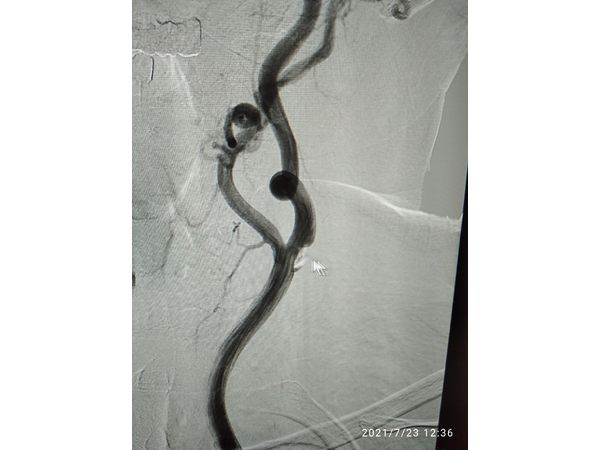

Результаты лабораторных исследований в пределах нормы. Ангиография сонных артерий подтвердила диагноз.

Диагноз

Атеросклероз брахиоцефальных артерий. Кинкинг внутренней сонной артерии с обеих сторон (аномальное удлинение, извитость и перегибы при патологическом строении стенки). Стеноз общей сонной артерии до 30 % слева. Сосудистая мозговая недостаточность IV степени (перенесённый инсульт).